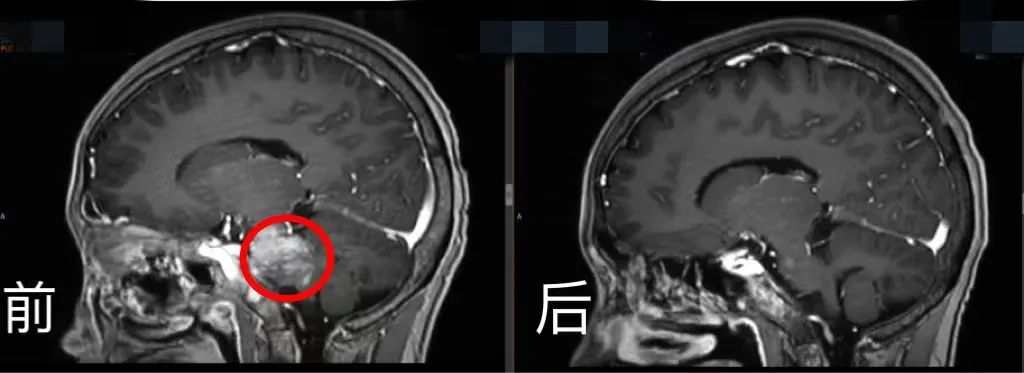

此時,小玉身體里的腫瘤轉移到腦部,腫瘤又變得猖獗。病情加重時,小玉再次暴瘦。血腦屏障的存在導致大多數藥物難以進入大腦。如何突破這一難題?

腦部CT前后對比。四川省腫瘤醫院供圖

經過2周的院內嚴密監測護理,小玉沒有發生細胞因子釋放綜合征和神經相關毒性等不良反應,再次復查影像學病灶幾乎完全消失。